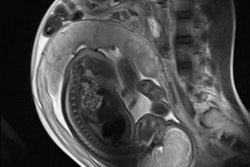

The normal fetal palate in the sagittal plane extends from the frenulum anteriorly at the upper lip as a continuous thin and linear hypodense structure, ending at the soft palate, which parallels the contour of the tongue to the level of the nasopharynx. The primary palate lies anteriorly and should blend seamlessly with the secondary palate, which is centered above the tongue. The incisive foramen is not identifiable on fetal MRI. The palate divides the nasal from the oral cavity and is best seen when surrounded by adjacent high T2-signal amniotic fluid.

On coronal T2-weighted images, the palate forms a continuous upward arch paralleling the expected contour of the tongue surface and a midline perpendicular intersection with the cartilaginous fetal nasal septum, they continued. More anteriorly, the upper and lower lips can be seen as a continuous ring of soft tissue.

On axial T2-weighted images, the overlying facial soft tissues should be uninterrupted at the level of the maxilla/alveolar ridge. The underlying horseshoe-shaped alveolar ridge contains hyperintense tooth buds, which should be bordered by an intact continuous low-signal border.

Involvement can be unilateral or bilateral and can also involve the primary palate as a full-length defect, they stated. A cleft involving this area cannot be visualized on ultrasound but can be assessed on fetal MR as loss of the expected hypodense stripe on T2-weighted imaging. Hence, an open communication now lies between the nasopharyx and oropharynx, which can cause a superior bulge of the tongue into the gap. With bilateral involvement, the central protruding premaxillary segment can again be seen, they concluded.